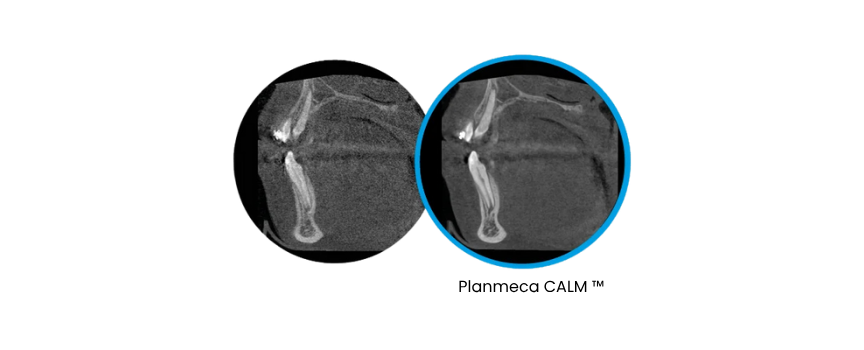

• Technologia Planmeca CALM® koryguje ruch pacjenta, eliminując rozmazania.

Planmeca CALM®, to innowacyjny sposób usuwania artefaktów z obrazów CBCT powstałych w wyniku poruszenia się pacjenta. Algorytm ten dostępny jest opcjonalnie dla wszystkich oferowanych przez nas unitów 3D.